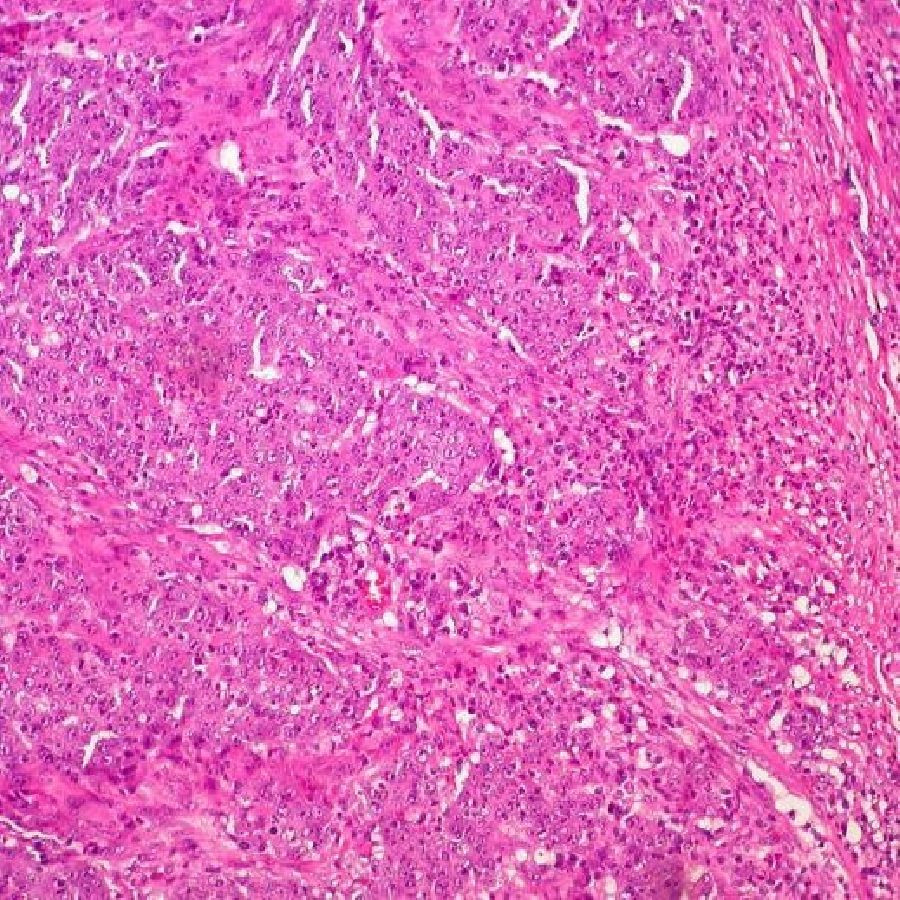

Los científicos de City of Hope, un centro de tratamiento e investigación biomédica independiente para el cáncer, la diabetes y otras enfermedades potencialmente mortales, en Estados Unidos, han desarrollado un virus que mata el cáncer que podría algún día mejorar la capacidad del sistema inmunológico para erradicar tumores en pacientes con cáncer de colon, según un estudio en publicado en `Molecular Cancer Therapeutics`, una revista de la Asociación Americana para la Investigación del Cáncer.

La investigación preclínica es un primer paso para demostrar que el virus oncolítico CF33 de City of Hope puede atacar tumores difíciles de tratar que "esposan" el sistema inmunológico y evitan que las células T activen el sistema inmunológico para matar las células cancerosas. Más específicamente, los investigadores demostraron en modelos de ratón que CF33 parece aumentar la expresión de PD-L1 en las células tumorales y hace que mueran de una manera que estimula la afluencia de células inmunes activadas.